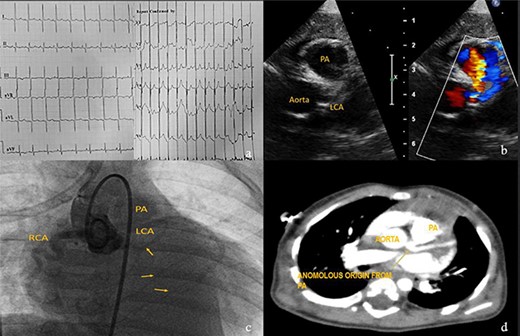

Case 4

Eight-month-male child admitted at a pediatric hospital for pneumonia and was referred to our pediatric cardiologist for cardiomegaly in his chest X-ray. ECG showed characteristic deep ‘q’ waves in Leads I, aVL, V5–V6 suggestive of anterolateral ischemia. Diagnosis of ALCAPA was suspected on echocardiography and confirmed on CT and root angiogram. His CT showed anomalous origin of left coronary from posterior sinus of PA and the aortic root angiogram spectacularly revealed retrograde flow from RCA to left system draining into the PA, as shown in Fig. 5. With only an ejection fraction (EF) of 20% due to coronary steal, child was scheduled for surgery at an earliest date possible following resolution of pneumonia. He underwent Modified Takeuchi repair with autologous pericardium used for creation of intrapulmonary tunnel with augmentation of PA. LV was noted to be stiff intraoperatively. First POD echo showed severe LV systolic dysfunction and severe MR. On second day, his blood pressure dropped requiring escalation of ionotropes. Veno-arterial extracorporeal membrane oxygenation (ECMO) support via central cannulation started, which improved his hemodynamics. Although successfully taken off the ECMO support on fifth POD, he developed sepsis and despite aggressive treatment with appropriate antibiotics, he developed multi organ dysfunction syndrome and succumbed on 16th POD.

Investigations for diagnosis of ALCAPA. (a) ECG showing characteristic findings. (b) Echocardiography. (c) Aortic root angiogram showing coronary draining into PA. (d) CT angiogram.

Bland et al. in 1933 first described clinical features with autopsy study of ALCAPA, and hence it is also named as Bland–White–Garland Syndrome [18]. Its pathophysiology principally lies in coronary steal from high pressure left coronary artery to low pressure PA[19] causing infarction of the antero-lateral free wall, congestive heart failure, ischemic mitral regurgitation. Mortality is almost 100% in untreated cases as circulation entirely depends on collaterals from RCA [20]. Ideal management is to establish dual coronary circulation which can be either by coronary translocation to aorta, bypass using subclavian or internal mammary artery, Modified Takeuchi procedure which creates and intrapulmonary tunnel and of historical interest proximal ligation of left system [21]. Takeuchi procedure is the procedure of choice when the LCA is far from aorta usually in non-facing sinus, and the technical details are depicted in Fig. 6. Lange et al. [22] in their study reported 30-day mortality of 14.3% and EF of <35% as independent predictor of mortality, the child in this study had an EF of 20%.